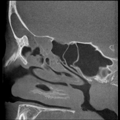

Bilder NNH

Kuhn'sche Zelle Mukozele SH Knochenneubildung Stirnhöhle sagittal Concha bullosa radikuläre Zyste